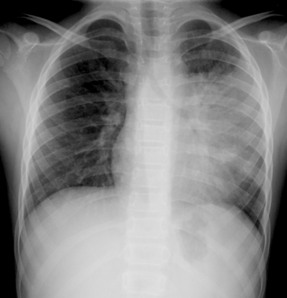

CASO 2 Neumonía |